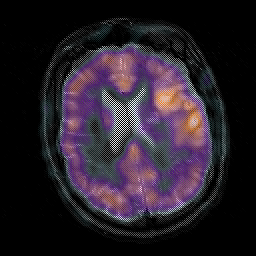

Subacute Stroke, overlay -- Slice #16

[Home][Help][Clinical] Slice 16